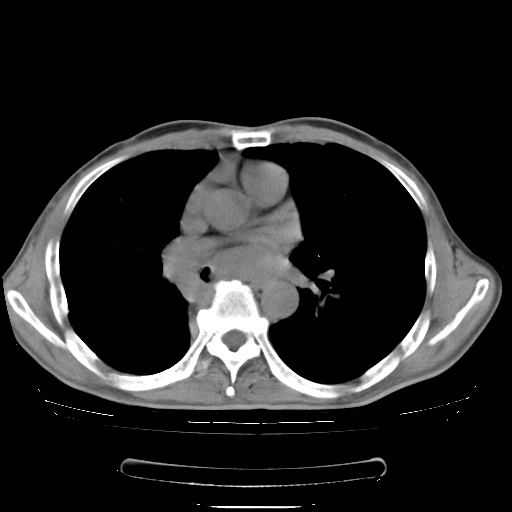

男性患者,63岁。右侧胸背部疼痛2月,加重一周。

考虑:右肺中央型肺癌并右肺下叶不张;两肺尖继发性肺结核。

还有----下叶不张   挺典型

右下中央型肺癌伴肺内纵膈转移。

右下肺中心型肺癌并肺不张

纵隔淋巴结转移

右肺下叶支气管狭窄闭塞,右下肺不张,气管前间隙淋巴结肿大,两上肺散在分部粟粒灶,沿肺血管支气管束分部,血管支气管束走形较为光滑。考虑右肺中心型肺癌合并肺不张,纵隔淋巴结转移,两上肺癌性淋巴管炎

右肺下叶中心性肺癌并纵隔淋巴结转移,左侧肋骨转移。双肺上叶继发性结核表现。

1)右肺下叶中心性肺癌并纵隔淋巴结转移,两肺转移,左侧肋骨转移。2)双肺上叶继发性结核。

右肺下叶中心性肺癌并纵隔淋巴结及两肺、左侧肋骨转移。双肺上叶继发性结核表现。